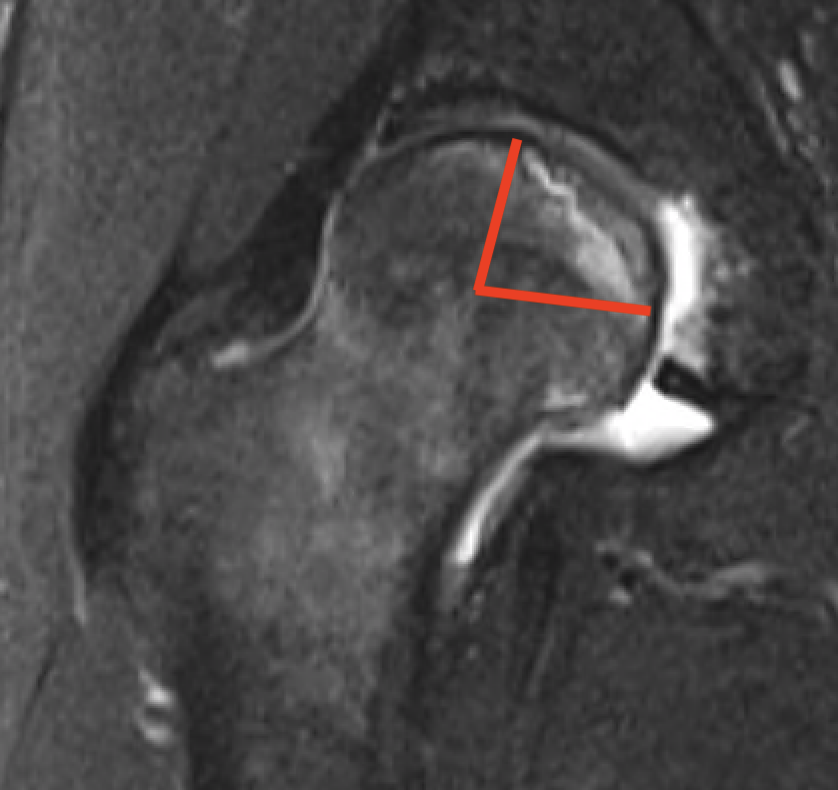

Modified Kerboul Combined Necrotic Angle (CNA)

Adding the arc of the femoral head necrosis

- mid-sagittal and mid-coronal MRI

- low risk collapse: < 190 degrees

- moderate risk collapse: 190 - 240 degrees

- high risk collapse: > 240 degrees

Kerboul CNA

- CNA > 240: 100% collapse

- CNA 190 - 240: 50% collapse

- CNA < 190: 0% collapse